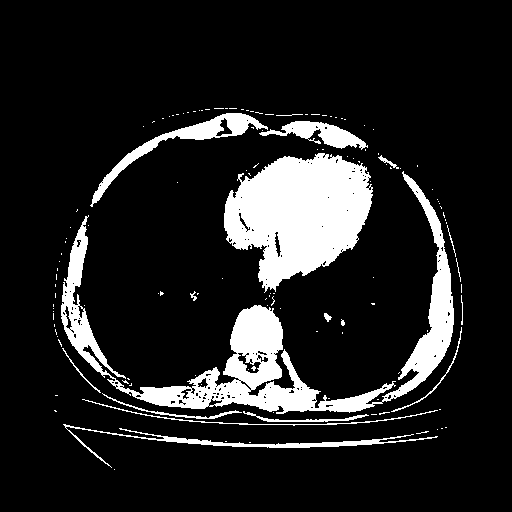

Image Grid

4Γ—3 grid: Rows show different image types (Original NATIVE, Reconstructed NATIVE, Original VENOUS, Generated VENOUS), Columns show windowing techniques (No Window, Lung Window, Mediastinum Window)

Generated VENOUS CT scan (A→B translation)

Full window (WL 1023.5, WW 4095 β†’ Low βˆ’1024, High +3071)

Actual HU range: [-1024.0, 3071.0]